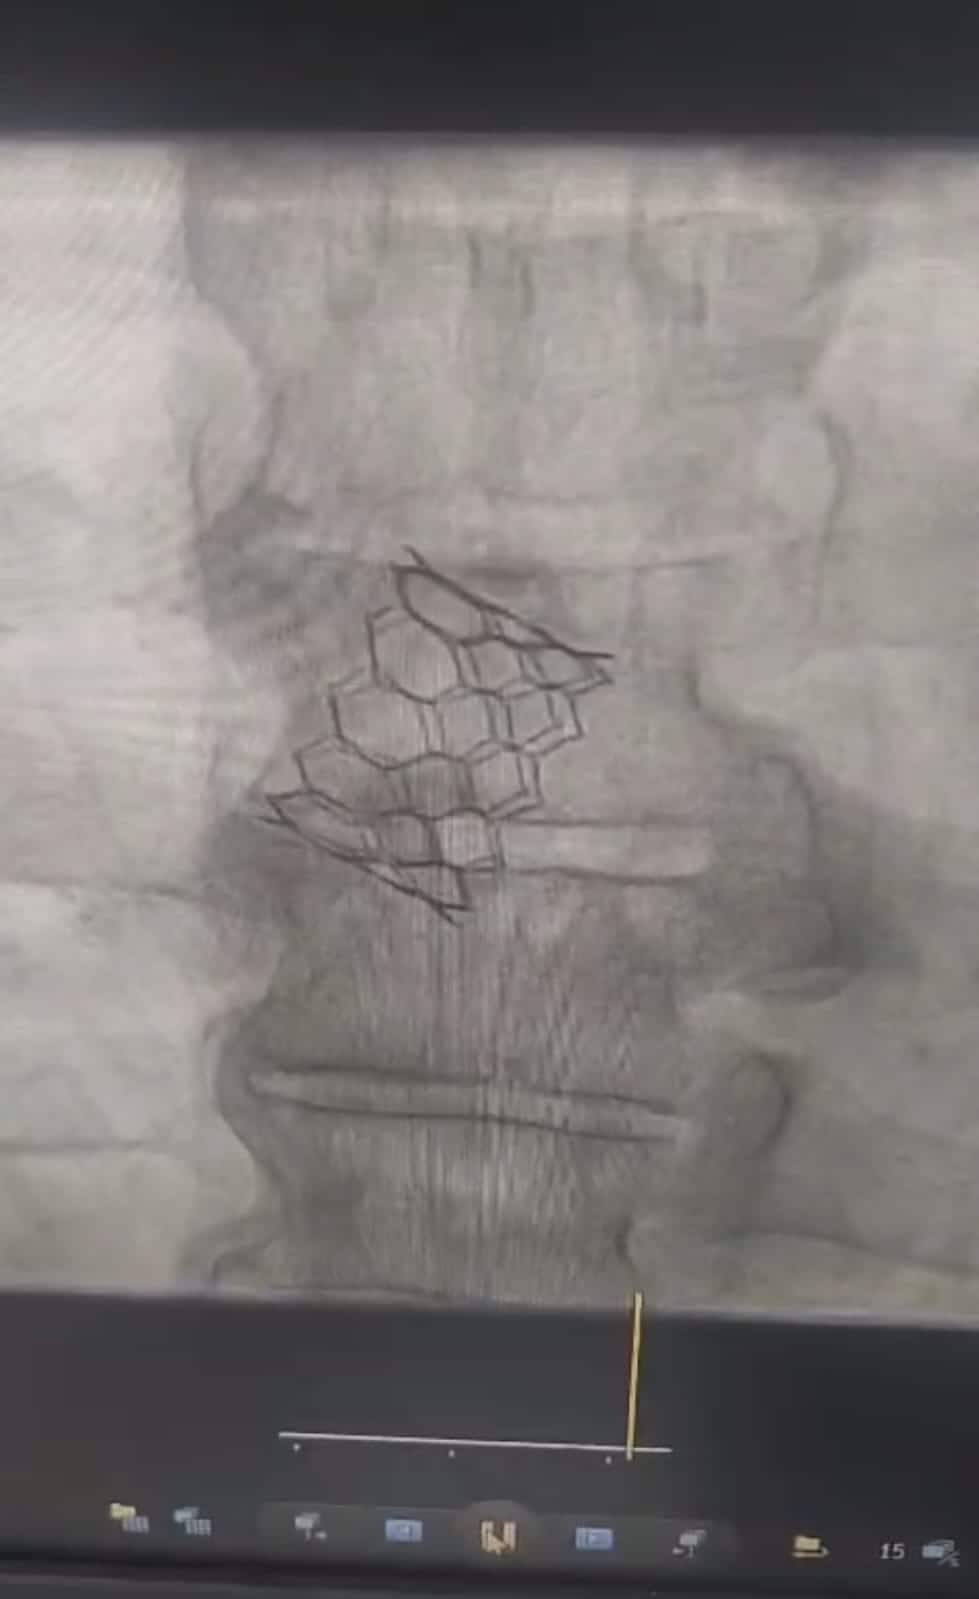

ಗದಗ: ಗದಗ ಜಿಲ್ಲಾ ಆಸ್ಪತ್ರೆ ಕೆ.ಎಚ್. ಪಾಟೀಲ ವೈದ್ಯಕೀಯ ವಿಜ್ಞಾನಗಳ ಸಂಸ್ಥೆಯ ಕ್ಯಾಥ್‌ಲ್ಯಾಬ್‌ನಲ್ಲಿ ಮೊಟ್ಟ ಮೊದಲ ಬಾರಿಗೆ ಟಿಎವಿಐ (ಟ್ರಾನ್ಸ್‌ಕ್ಯಾಥೆಟರ್‌ ಐಯೋಟಿಕ್ ವಾಲ್ವ್ ಇಂಪ್ಲಾಂಟೇಶನ್) ಹೃದಯ ಶಸ್ತ್ರಚಿಕಿತ್ಸೆ ಯಶಸ್ವಿಯಾಗಿ ನಡೆಸಲಾಗಿದೆ.

ಹೃದ್ರೋಗ ತಜ್ಞ ಡಾ. ಸಂಜೀವಕುಮಾರ ಚಿಂತಾಮನಿ, ಡಾ. ಮಂಜುನಾಥ ಹಿರೇಮಠ ಸಹಕಾರದಲ್ಲಿ ಬೆಂಗಳೂರಿನ ಟಿಎವಿಐ ತಜ್ಞ ವೈದ್ಯ ಡಾ. ವಿಕ್ರಮ ಪಾಟೀಲ ನೇತೃತ್ವದ ವೈದ್ಯಕೀಯ ತಂಡ 55 ವರ್ಷದ ವ್ಯಕ್ತಿಗೆ ಸಂಕೀರ್ಣವಾದ ಹೈಬ್ರಿಡ್‌ ವಿಧಾನದ ಮೂಲಕ ಯಶಸ್ವಿ ಹೃದಯ ಮಹಾಪಧಮನಿಯ ಕವಾಟ ಬದಲಾವಣೆ ಮಾಡಿದ್ದಾರೆ.

ಗದುಗಿನಲ್ಲಿ ಮೊದಲು: ಬೆಂಗಳೂರಿನ ಜಯದೇವ ಆಸ್ಪತ್ರೆ ಹೊರತುಪಡಿಸಿ ರಾಜ್ಯದಲ್ಲೇ ಸರ್ಕಾರಿ ಆಸ್ಪತ್ರೆ ಹಾಗೂ ಇತರೆ ಜಿಲ್ಲೆಯ ವೈದ್ಯಕೀಯ ವಿಜ್ಞಾನಗಳ ಸಂಸ್ಥೆ ಕ್ಯಾಥ್ ಲ್ಯಾಬ್‌ವೊಂದರಲ್ಲಿ ನಡೆಸಿದ ಮೊದಲ ಯಶಸ್ವಿ ಶಸ್ತ್ರಚಿಕಿತ್ಸೆ ಎಂಬ ಹೆಗ್ಗಳಿಕೆಗೆ ಈ ಚಿಕಿತ್ಸೆ ಪಾತ್ರವಾಗಿದೆ. ಇದು ತೆರೆದ ಹೃದಯ ಶಸ್ತ್ರಚಿಕಿತ್ಸೆ ಇಲ್ಲದೆ, ತೊಡೆಯ ಮೂಲಕ ಕ್ಯಾತಿಟರ್ ಬಳಸಿ ಹೃದಯದ ಕವಾಟ ಬದಲಾಯಿಸುವ ಅತ್ಯಾಧುನಿಕ ಮತ್ತು ಕನಿಷ್ಠ ಅಪಾಯದ ಚಿಕಿತ್ಸಾ ವಿಧಾನವಾಗಿದೆ.